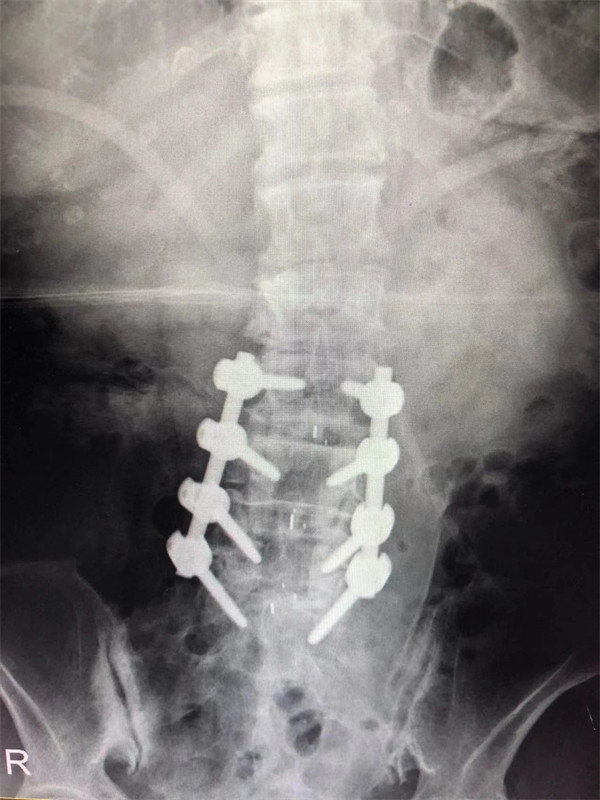

手術后↓

戈才華主任團隊討論病情及手術風險,并與麻醉科醫(yī)生多次討論術中麻醉風險,經(jīng)過詳盡周密的布置之后,最終給阿婆在全麻下進行腰3/4,4/5,腰5/骶1腰椎椎體間融合術。

術后阿婆腰痛伴雙下肢疼痛明顯緩解,術前疼得晚上睡不著覺的情況不再出現(xiàn)。阿婆和家屬連聲道謝,對醫(yī)生的治療技術和服務贊不絕口。